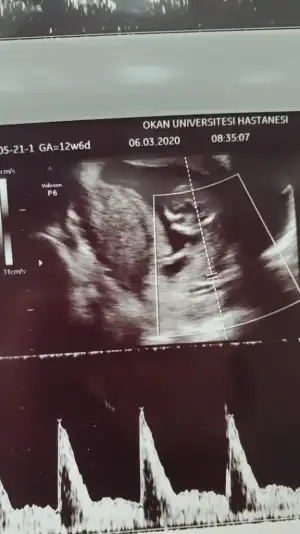

Kız gibiIkra meyra tekrar usg paylaşın demiştiniz sat a göre 12+1 ultrasona göre 12+6 çıktık ❤Pazartesi tekrar gideceğim ama bunu da atmak istedim belki bir tahmin olur

![]()

11 12 13 haftalar nub için uygun şimdilik sanki erkek gibi gibi dediğimiz usgleri paylaşırmısınızIkra meyra bir bakarmısın canım

Malesef bir tek bu var 11+5 olarak başka yok11 12 13 haftalar nub için uygun şimdilik sanki erkek gibi gibi dediğimiz usgleri paylaşırmısınız